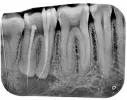

Первое фото - это снимок в 1-ое посещение (врач смотрел, как прошли каналы). Второе фото - это снимок во 2-ое посещение (пломбирование каналов).

- Пломбировочный материал вышел за пределы верхушки корня в кисту. Это нормально?

Небольшое выведение пломбировочного материала за верхушку корня допустимо в случае наличия периапикального воспаления.